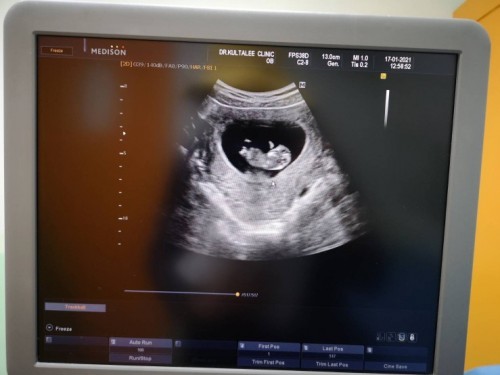

16+1ยังไม่ทราบเพศค่ะใครดูออกบ้าง ช่วยตอบหน่อยค่ะ